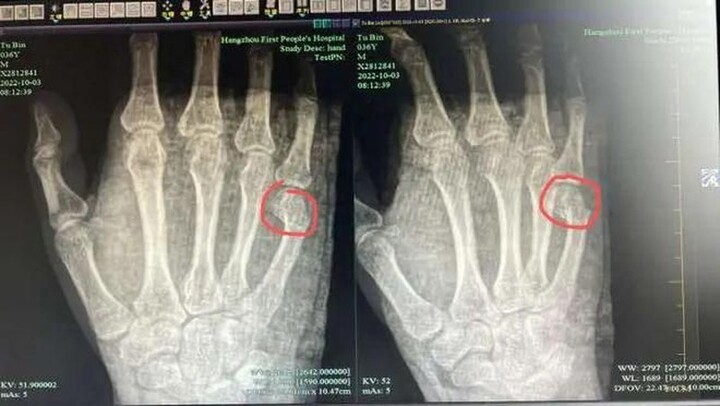

Hành động trong cơn nóng giận khiến người bố bị đau và sưng tấy lòng bàn tay phải, cần nhập viện để làm tiểu phẫu.